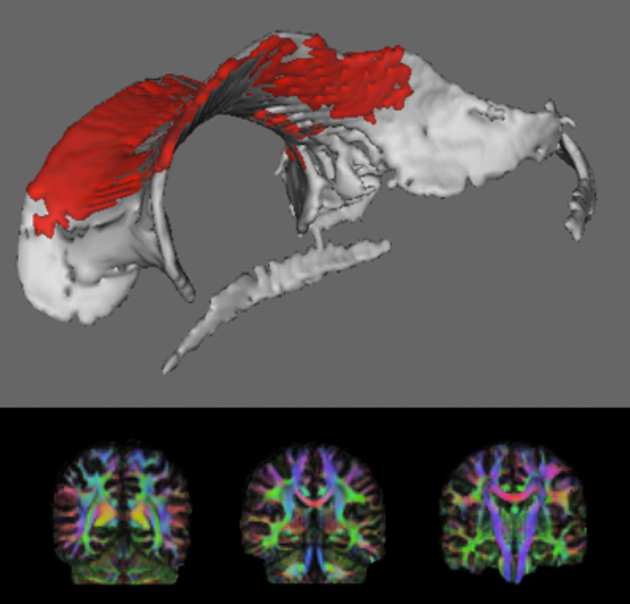

Traumatic brain injury (TBI) is the most common cause of death and disability in young adults. It is most commonly caused by road traffic accidents and assaults. Patients can experience problems with concentration, attention span, and memory. This cognitive impairment poses an immense burden to well-being, and leads to significant economic and social consequences. In military personnel, TBI may occur following blast injury, which has become the signature injury from the current conflicts in Iraq and Afghanistan. Approximately 25% of TBI patients improve but an equal number deteriorate over time. We know little about why patients vary so much in how they recover. Crucially, we have no treatments to improve cognitive impairment and brain recovery after TBI. When we are injured our bodies mount an inflammatory response to start the healing process. This may be helpful initially but if this process continues it can be damaging. Recently, using a Positron Emission Tomography (PET) scan, abnormal persistent brain inflammation – chronic neuroinflammation – has been detected following TBI. Little is known about how chronic neuroinflammation following TBI relates to brain recovery. We will use two types of brain scan to investigate chronic neuroinflammation and brain recovery: PET and Magnetic Resonance Imaging (MRI). PET scans allow us to measure inflammation directly. MRI scans measure brain structure and function. We will assess psychological and social recovery. We are also investigating whether particular genes lead to poor outcomes and whether the metabolic syndrome, a condition causing long-term inflammation in the body, also is associated with chronic neuroinflammation.